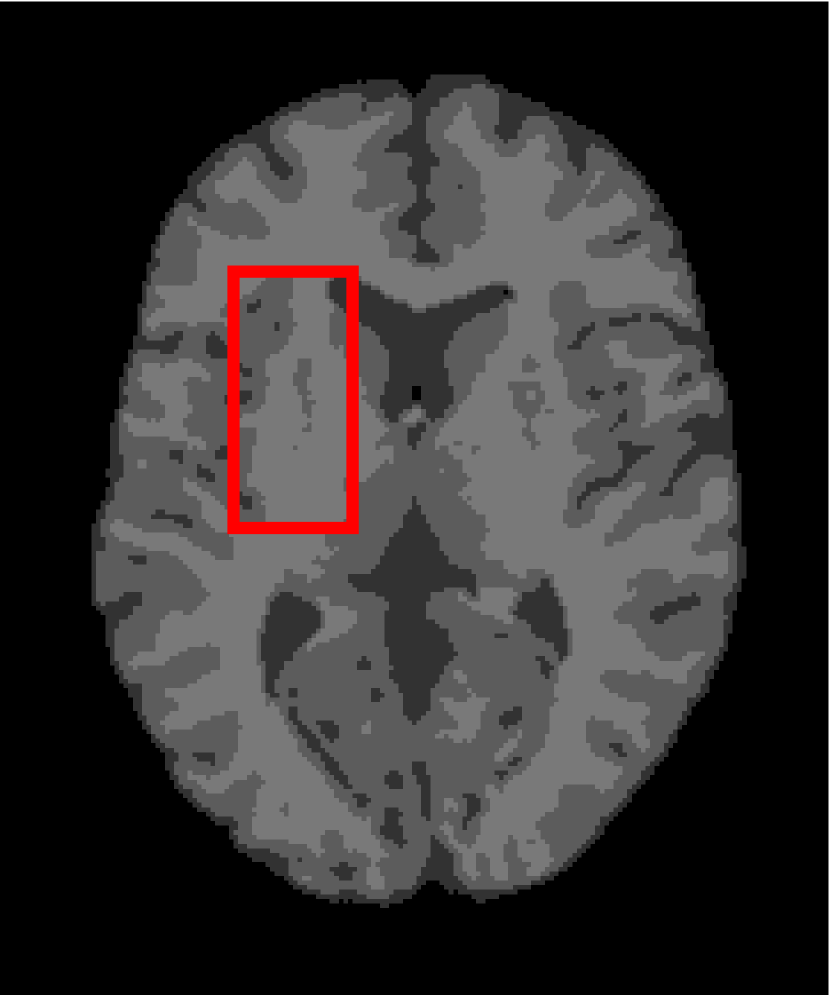

Next, we representatively segment five medical images from BrianWeb. They are represented as five slices in the axial plane with a sequence of 70, 80, 90, 100 and 110, which are generated by T1 modality with slice thickness of 1mm resolution, 9% noise and 20% intensity non-uniformity. Here, we set c=4𝑐4c=4 for all cases. The comparison between WRFCM and its peers are shown in Fig. 9 and Table II. The best values are in bold.

Figure 9: Segmentation results on five medical images. The parameter: ϕ=5.35italic-ϕ5.35\phi=5.35. From top to bottom: noisy images, ground truth, and results of FCM_S1, FCM_S2, FLICM, KWFLICM, FRFCM, WFCM, DSFCM_N, and WRFCM.

By a view of the marked red square in Fig. 9, we find that FCM_S1, FCM_S2, FLICM, KWFLICM and DSFCM_N are vulnerable to noise and intensity non-uniformity. They give rise to the change of topological shapes to some extent. Unlike them, FRFCM and WFCM achieve sufficient noise removal. However, they produce overly smooth contours. Compared with its seven peers, WRFCM can not only suppress noise adequately but also acquire accurate contours. Moreover, it yields the visual result closer to ground truth than its peers. As Table II shows, WRFCM obtains optimal SA, SDS and MCC results for all five medical images. As a conclusion, it outperforms its peers visually and quantitatively.